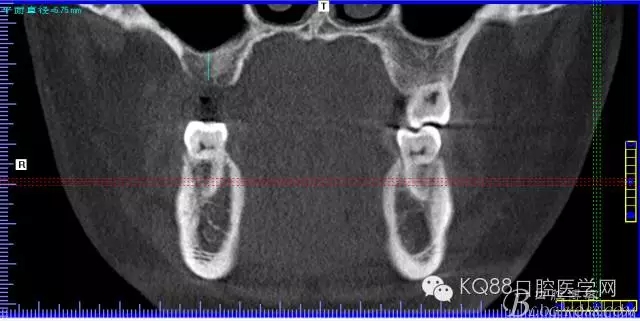

下面是拔牙前 CBCT

清晰可見(jiàn)根尖部陰影區(qū)域明顯。遠(yuǎn)中頰根

近中頰跟,同時(shí)可以看出離上頜竇比較近,且伴有骨缺損。

這個(gè)切面可以看到根裂。